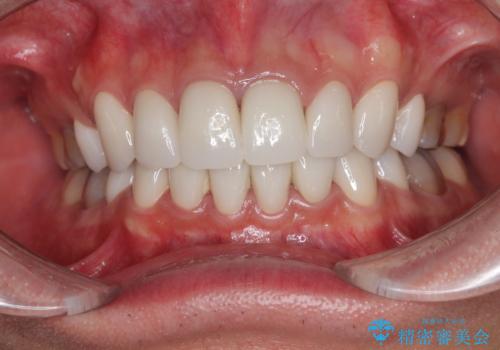

薬剤の影響で変色した歯を自然に オールセラミッククラウンによる審美歯科治療

- 口元の突出感を改善するための抜歯矯正を終えた患者様ですが、幼少期からの変色した歯をセラミッククラウンにて自然な色合いに変えていくこととしました。

口を開けたときに目につく範囲を希望されたため上下ともに8本ずつをオールセラミッククラウンによる補綴治療を行うこととしました。

近年では大変珍しいですが、胎児あるいは乳幼児期の抗生物質の影響で永久歯が変色してしまうことがあります。

ホワイトニングでの改善は期待できないため、オールセラミッククラウンによる補綴治療が必要となります。